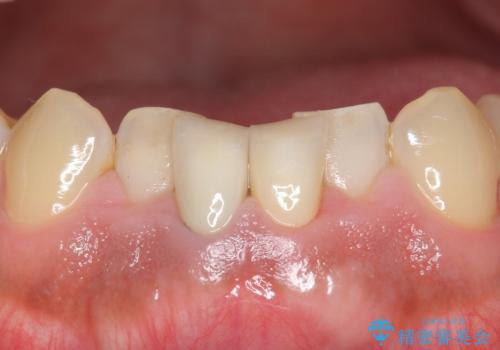

- 下の前歯の色が気になることを主訴に来院された患者様です。

下の前歯は金属の土台により黒くなり、隣の歯も神経が死んで暗く変色していました。

神経が死んでいる歯の根管治療を行った後、セラミッククラウンによる補綴治療を行いました。

比較的短期間(2ヶ月、来院回数:5回)で治療が終わったこと、また自然な仕上がりと使用感にご満足頂けました。

~被せ物の種類~

ジルコニアクラウン スタンダード